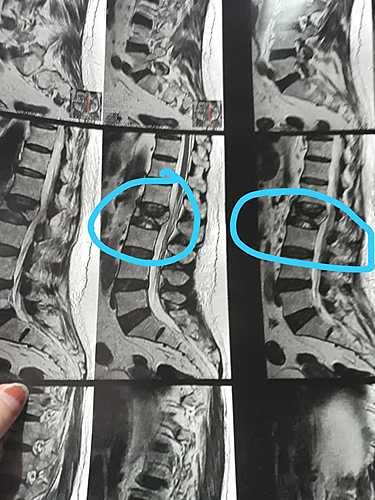

Trata-se de uma fratura complexa de vértebra lombar, com esmagamento e tensionamento da medula espinhal.

Como os médicos não identificaram a origem da fratura em sua vértebra lombar, foi solicitado uma biópsia da coluna como exame complementar e uma cirurgia (vertebroplastia).